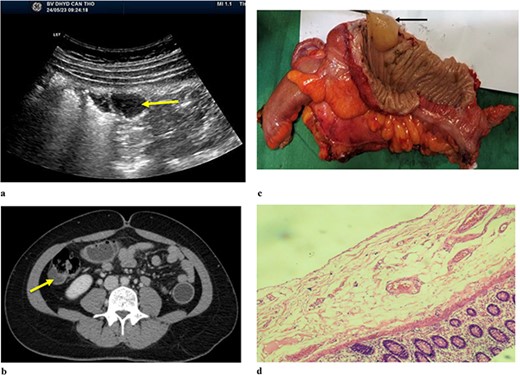

A 21-year-old male patient presented to the emergency department due to colicky right iliac fossa pain with progression to distension, nausea, vomiting, and obstipation. After 72 hours of attempting self-medication at home without any improvement, his family decided to take him to the hospital. During the physical examination, the patient exhibited a body temperature of 39°C, and his tachycardia was 112/min, and blood pressure was 100/70 mmHg. Abdominal ultrasound (Fig. 1) was reported as the right iliac region has an intestinal structure ~81 × 31 mm in size, with a wall thickness of 9 mm and continuous with an anechoic cyst-like structure ~29 × 24 mm in size, with a hypoechoic wall ~5 mm thick. There is little fluid around. CT scan (Fig. 1b) revealed thickening of the small intestinal wall and ileal cyst dilation with bowel ischaemia. Based on the clinical and radiographic findings, he was diagnosed with strangulated bowel obstruction. The patient proceeded to have an explorative laparotomy performed. Intraoperative findings indicated that an isolated tubular ileal duplication had become twisted, resulting in necrosis of the adjacent small intestine extending ~30 cm (Fig. 1c). Surgical intervention involved performing a segmental resection of the bowel and cyst, followed by reconstruction using a side-to-side anastomosis technique. On histopathological examination (Fig. 1d) showed a separation of the ileal duplication cyst. The inner lining of the cyst revealed mucinous epithelium with mucin. He had a successful recovery and was discharged after 7 days.

(a). Ultrasound shows an arrow pointing to anechoic structure with hypoechoic wall. (b) Axial CT scan showing an arrow pointing to an ileal cyst dilation with bowel ischaemia. (c) Intraoperative image of small bowel ischaemia with an arrow pointing to the strangulated location. (d) Postoperative image shows ileal duplication cyst.